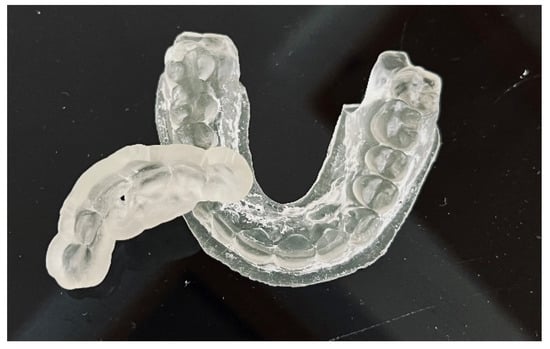

The guide should be printed from resin dedicated for surgical guides—a class IIa product that can be sterilized and safely used in the oral cavity (Figure 6) [22]. The entire digital workflow is presented in Figure 7.

Figure 6. Endodontic guide and patient’s upper arch 3D-printed model.

After the implant position was accepted by a clinician, an endodontic guide (teeth-supported) was designed for a sleeveless, static navigation of the image obtained from an intraoral scan (Figure 12). The guide covered the labial and palatal surfaces of the adjacent teeth (13-23) to obtain adequate intraoral stabilization. The use of stabilizing pins is unnecessary in such cases. The guide tube was designed so that the top of the sleeve was 21 mm from the radiographically visible root canal lumen. The guide sleeve was 6 mm long and 1.5 mm in diameter. The endodontic guide was printed on a resin 3D printer (Phrozen Sonic Mini 4K) using a transparent resin designed for printing surgical guides (NextDent SG)—a class IIa product that can be used in the oral cavity (Figure 13). Post-processing was conducted in accordance with the resin manufacturer’s instructions to avoid dimensional changes [24]. A master model was printed to check the accuracy of the guide’s fitting (Figure 14).

Figure 13. Three-dimensional printed endodontic guide.

Figure 14. The three-dimensional printed guide and the patient’s model enabled us to check the accuracy of the guide and to practise proper drill insertion.